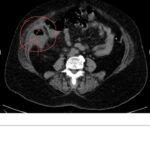

A perda auditiva pode ter diversas causas, uma delas é a esclerose. Essa doença é caracterizada pelo aumento da rigidez na cadeia dos ossos do ouvido, o que pode levar à perda de audição. O diagnóstico da esclerose é feito por meio da história do paciente e exames como a geometria e tomografia.

Para tratar a perda auditiva causada pela esclerose, uma das formas é a estapedectomia. Nesse procedimento, é realizada uma incisão no tímpano para confirmar o diagnóstico. Caso haja evidência da esclerose, é realizada a correção da rigidez usando uma prótese. Tudo é feito com a segurança da vida endoscopia.